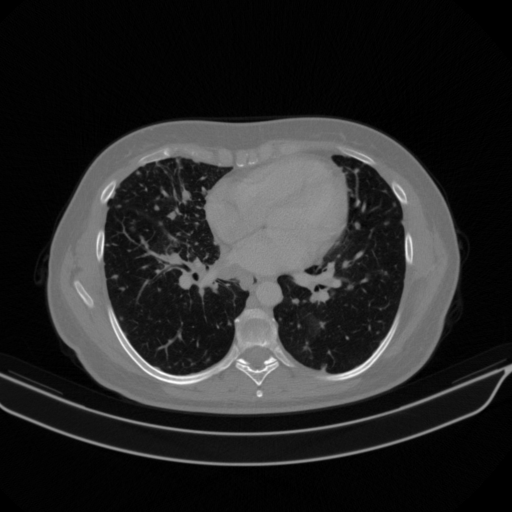

Original NATIVE CT scan (input)

No window - Raw intensity values

Lung window (WL -600, WW 1500 β†’ Low βˆ’1350, High +150)

Mediastinum window (WL 40, WW 400 β†’ Low βˆ’160, High +240)